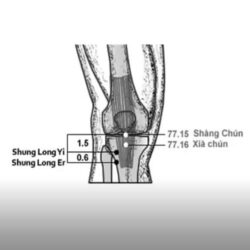

שילובי נקודות למחלות של האברים הפנימיים

מחלות של הריאות דלקת ריאות סרטן ריאות אמפיזמה שחפת אסטמה מחלות של הלב אנגינה פלפיטציות אנגינה פקטוריס (Myocardial Infarction) לב מוגדל (Cardiomegaly) שיתוק לבבי (Cardiac paralysis) כאב ברום הבטן (Epigastric pain) מחלות של הכבד וכיס המרה שחמת הכבד (Liver cirrhosis) צהבת (Hepatitis) דלקת של כיס המרה (Cholecystitis) אבן בכיס מרה מחלות של הטחול והקיבה טחול מוגדל (Abdominal […]